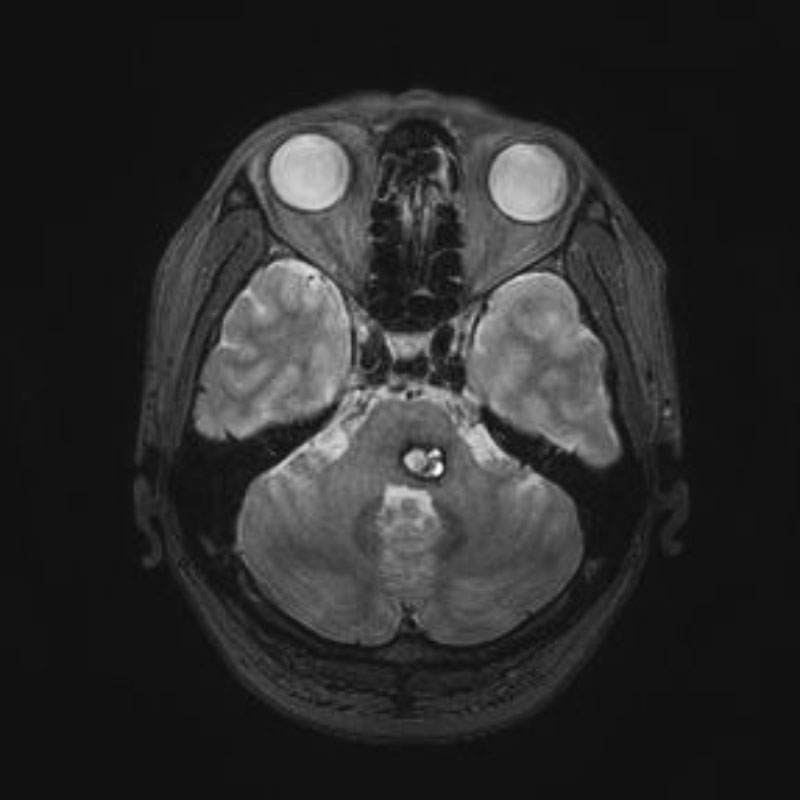

右側頭葉脳腫瘍

摘出術

南田/野本/佐伯